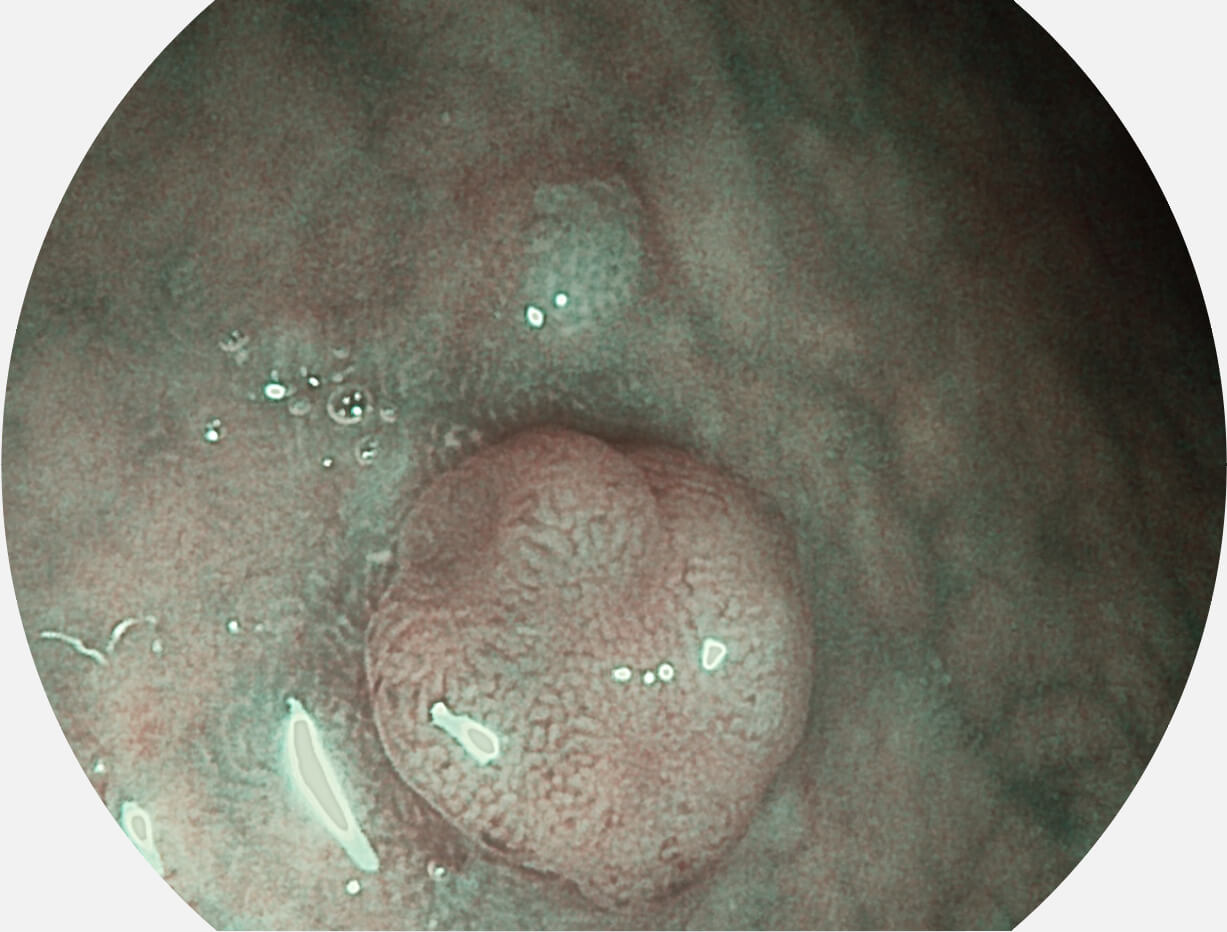

Versatile Intelligent Staining Technology, VIST

强调浅层黏膜结构的同时,保证照明亮度和提升浅层微血管与中层血管颜色对比度,病变边界更清晰。

白光图像